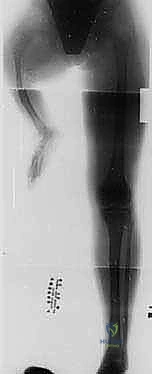

العرض السريري الأولي

يُظهر المرضى مجموعة واسعة من التشوهات التي تلاحظها العائلة فور الولادة. عادةً ما يُلاحظ قصر واضح في الطرف المصاب مقارنة بالطرف السليم. هذا القصر يزداد مع نمو الطفل. وغالبًا ما يكون هذا القصر مصحوبًا بتشوه في القدم يُعرف بـ "القدم الحنفاء المروحية" (Equinovalgus foot)، حيث تنحرف القدم للخارج وللأسفل. كما يمكن ملاحظة علامات جلدية مميزة مثل انخفاضات جلدية (Dimples) فوق الجزء الأمامي الأوسط من قصبة الساق، وهي علامة سريرية كلاسيكية لهذا المرض.

المرحلة الأولى: التخطيط ما قبل الجراحة

تبدأ الرحلة بتقييم شعاعي دقيق (أشعة سينية، وأحياناً رنين مغناطيسي MRI لتقييم الأربطة). يتم قياس التفاوت في طول الأطراف بدقة، وتحديد زوايا الانحراف. يجلس الدكتور هطيف مع العائلة في جلسة استشارية مطولة، يشرح فيها كل التفاصيل، ويجيب على كافة التساؤلات بأمانة طبية مطلقة، مما يزرع الطمأنينة في قلوب الآباء.